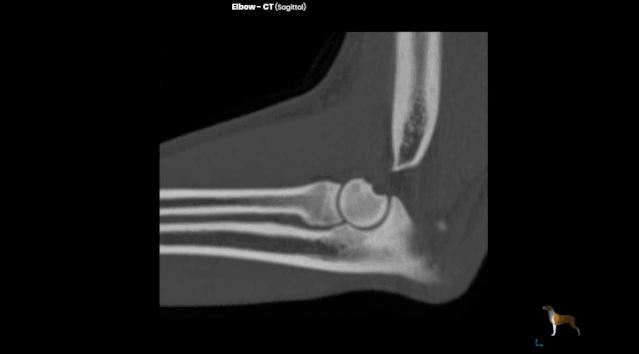

CT也是一种 X 线检查,它能对骨折部位进行多层的扫描,提供每一层的截面图像,使骨折的图像呈现避免了其他组织的干扰,更清楚地显示出来。在普通的X线片上显示不出来骨折都能在CT片上清楚地显示。